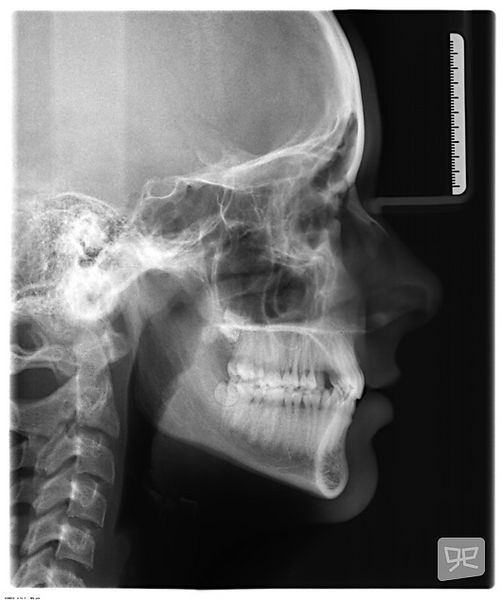

Gagnataka

Gagnatökutími er sú heimsókn sem er næst á eftir fyrstu skoðun.  Þá eru teknar ljósmyndir, röntgenmyndir af kjálkum og tönnum og að lokum tannmódel til greiningar á tönnum og biti.

Á þessum gögnum er svo meðferðaráætlun byggð.